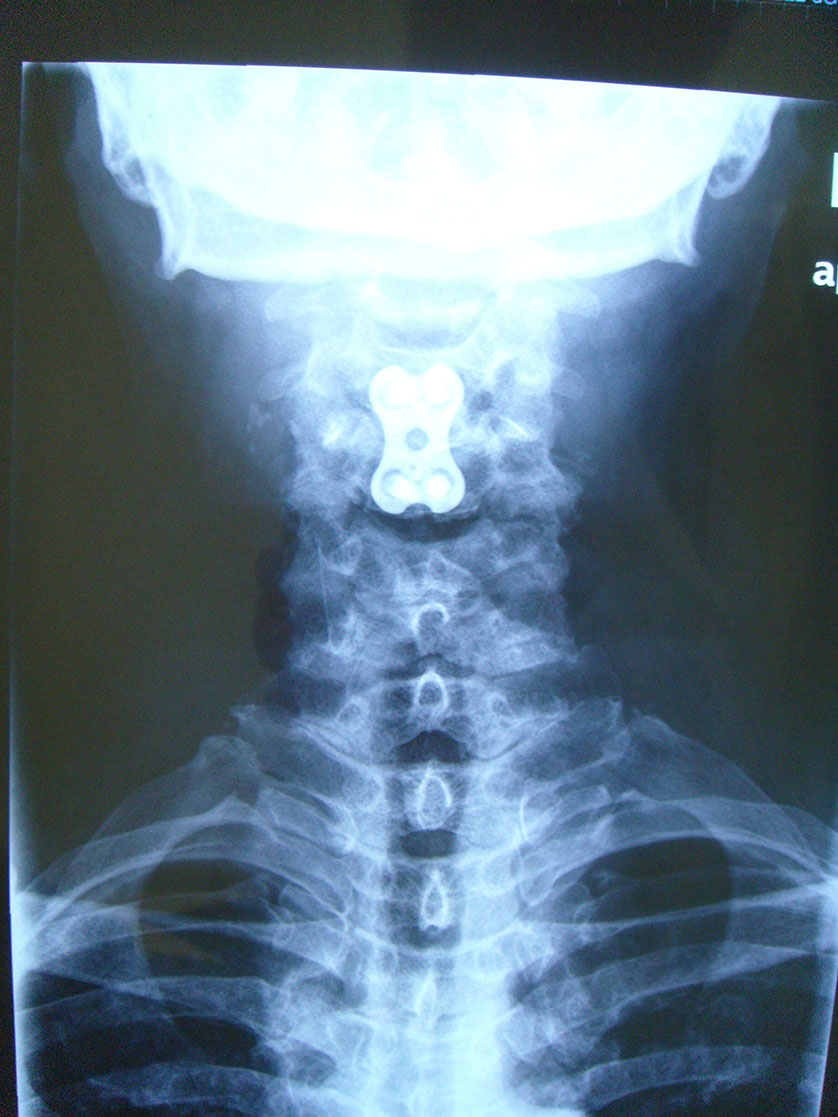

徐**,男性,于2006年2月24日因第3/4颈椎椎间盘突出症,颈椎前路椎间盘切除,同种异体骨椎体间植骨融合内固定手术,术后2个月,11个月及4年半随访植骨块愈合良好